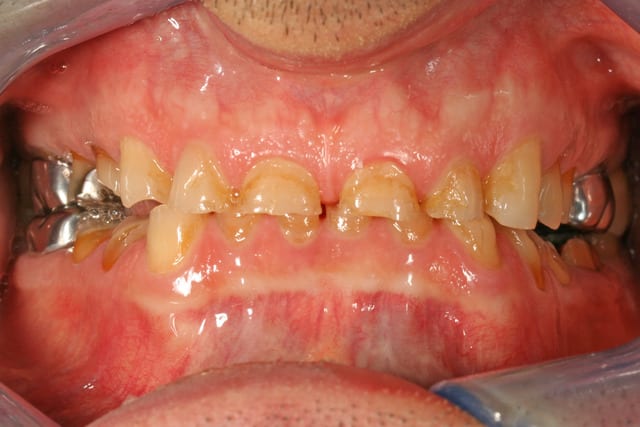

voilà un patient venu en urgence pour sa 36 descellée depuis plus d'un mois, que je n'ai pas pu resceller cause egression de la dent et couronne super fine que j'aurais trouée de partout en la retouchant

Puis je le vois en bilan, ou je vois qu'il est conscient de son problème, il me dit qu'il a déjà cherché des solutions, mais qu'à part deux dentistes qui lui ont fait des gouttières, qu'il a porté un peu mais qu'il a quittées au bout d'un moment, et une dentiste qui à botté en touche ... il n'a pas eu de solutions

je lui ai dit que de toutes façons il pouvait tout user avec son bruxisme (et je le lui redirais !)

les modèles d'étude

on voit bien l'abrasion liée au bruxisme

l'érosion liée à l'acidité (une bière tous les soirs avant le repas, une pomme tous les soirs en dehors du repas)

l'usure des prémos liée a de mauvaises habitudes dans son métier (tournevis ou stylo au coin de la bouche)